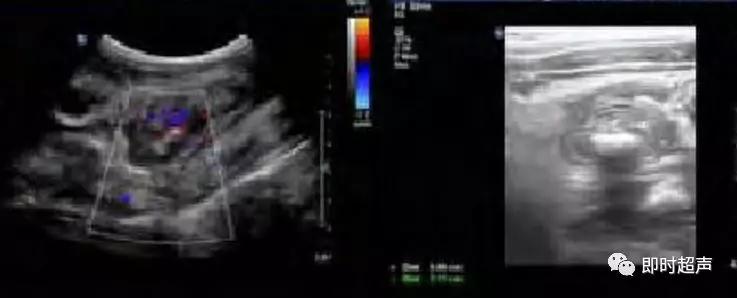

幽门纵切呈“宫颈征”。幽门横切面呈“靶环征”

幽门环形肌纵向呈低回声圆柱体

幽门环形肌“同心圆”征